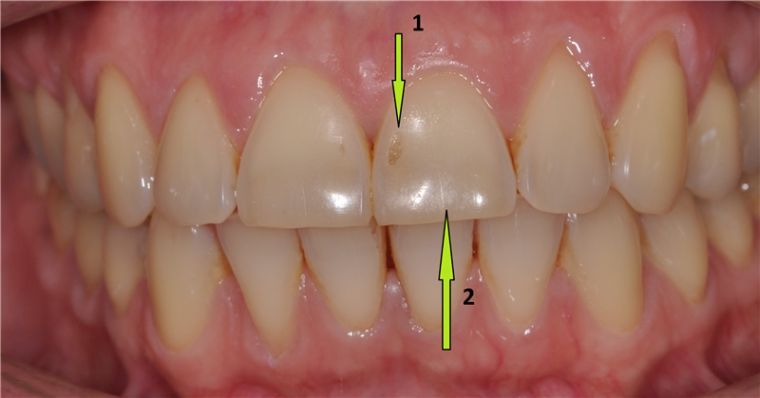

Эрозия чаще поражает зубы фронтальной группы (резцы, клыки, реже – премоляры). Основным клиническим признаком патологии являются дефекты или пятна, имеющие округлую, овальную или неправильную форму.

На начальных стадиях развития процесса определяется лишь небольшая утрата естественного блеска эмали. По мере развития эрозии пациенты предъявляют жалобы на боли от химических и термических факторов, а на эмали образуются дефекты с блестящим и ровным дном. Течение может быть активным и стабилизированным. Если процесс развивается медленно (стабильно), то больной может долгое время не обращать внимания на наличие патологии. Чаще всего к специалисту обращаются женщины, поскольку даже на ранних стадиях заболевание приводит к появлению косметического дефекта. Эрозия фронтальных зубов заметна при улыбке.

Заболевание выявляется в ходе осмотра при визуальном осмотре. Особенно хорошо дефекты становятся заметны после тщательного высушивания и обработки 5% настойкой йода. Раствор йода дает желто-коричневое окрашивание патологически измененной эмали.

Как выглядит эрозия зуба?

Эрозия зубов представляет собой кругообразный либо овальный дефект эмали, который расположен в максимально выпуклой области вестибулярной поверхности коронковой части в поперечном направлении. Ее основание достаточно гладкое, твердое и блестящее.